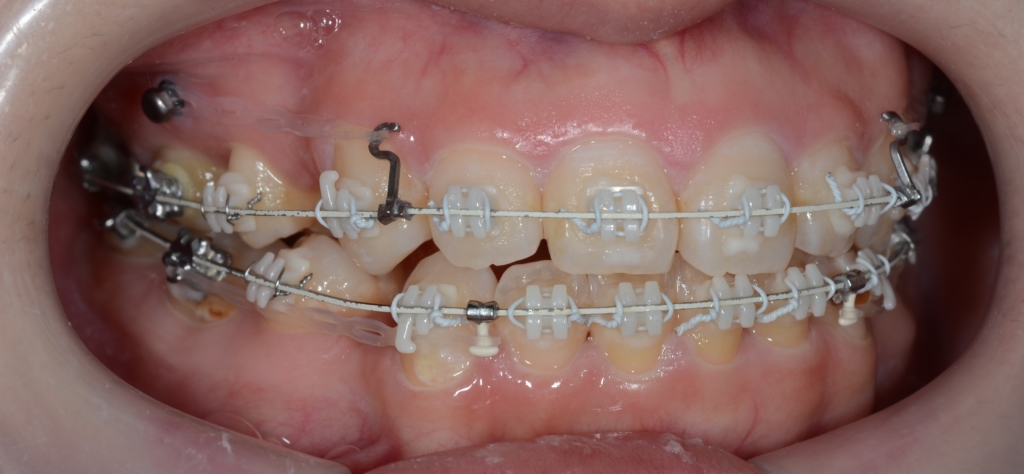

スイマセン・・・

この方の写真を探したのですが見つからないため、全く同じことをしている患者さんの写真を「イメージ写真」として代用しています。

上顎のアンカースクリューには、PLAS & 奥歯の内側にはパラタルバーを付けて

下顎のアンカースクリューには、よじったワイヤーフックを付けて

上下の歯列(歯並び全体)を出来るだけ後方へ引っ込めて行く「矯正力」を加えて、治療を再開しました。